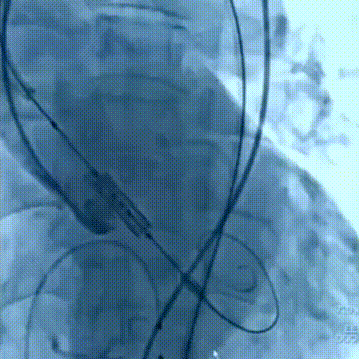

手术过程

患者全麻后,右侧股总动脉建立主入路,主动脉根部造影示主动脉瓣明显钙化伴重度狭窄。直头导丝跨瓣后,在超硬导丝支撑下,瓣膜输送系统顺利跨瓣。在180次/分快速心室起搏下,确定降压至50mmHg后选择20mm球囊进行预扩张。根据术前评估及球囊预扩情况,最终选择23mm Prizvalve®球扩瓣进行植入。

瓣膜释放

球囊预扩张

释放后造影